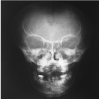

Thirteen years old female patient was referred to the periodontal clinic after her deciduous teeth were extracted to improve her oral hygiene and then to be referred to prosthetic clinic in order to construct upper and lower removable partial denture. After extra and intra oral examination; the patient had the classical signs of CCD: frontal bossing and hypertolerism with low nasal bridge (depressed nasal bridge). Attempt to place her shoulder adjacent to the midline, relatively short stature (Figure 1). Chest X-ray revealed hypoplastic clavicle with small high lying scapula (Figure 2), anterioposterior skull view showed macrcephale with widened anterior fontanel and sagital suture (Figure 3).

Figure 3. Anterioposterior skull view